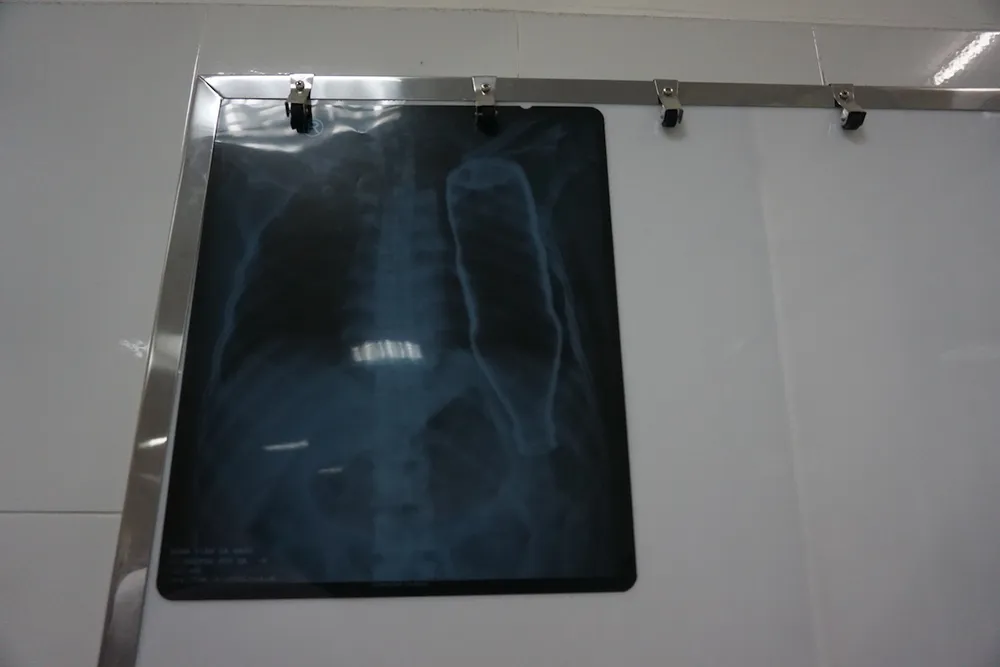

Sau khi tiếp nhận bệnh nhân, BV đã tiến hành chụp X-quang và CT, các bác sĩ ngỡ ngàng khi thấy một vỏ chai thủy tinh còn nguyên vẹn trong lồng ngực bệnh nhân B.

Được biết do say rượu nên ông B. vấp ngã và bị vỏ chai nước khoáng đâm lọt luôn vào lồng ngực. Ảnh: KIỀU VŨ